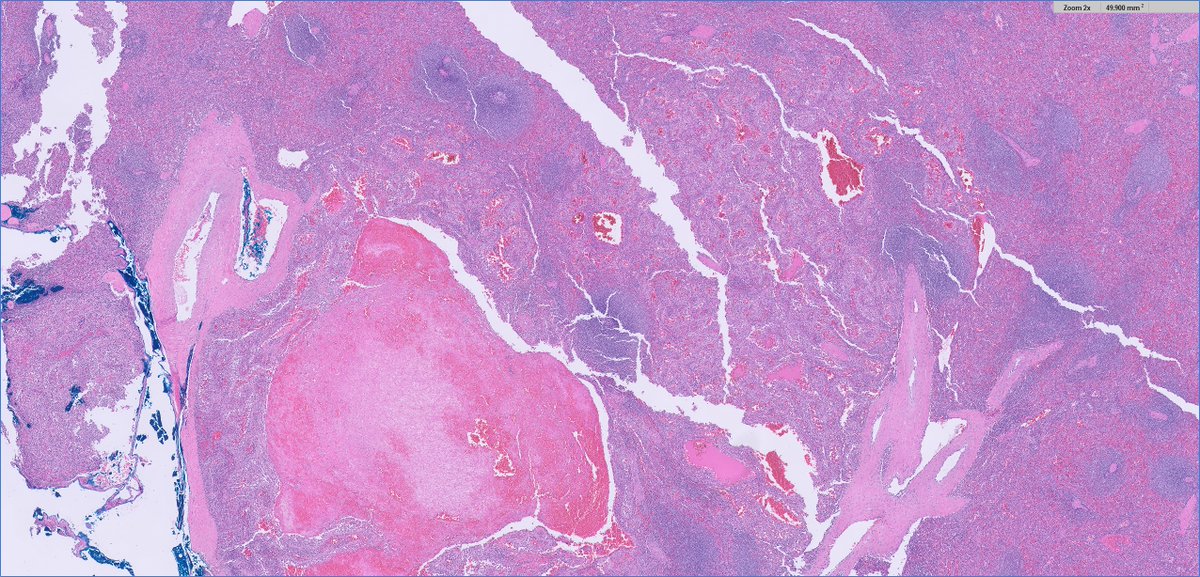

💎 Papillary Renal Cell Carcinoma (PRCC) in Acquired Cystic Kidney Disease ⚓️ Definition: PRCC is a malignant epithelial tumour with papillary or tubulopapillary architecture — the second most common renal cell carcinoma (13–20%). ⚓️ Association: Seen in patients with end-stage